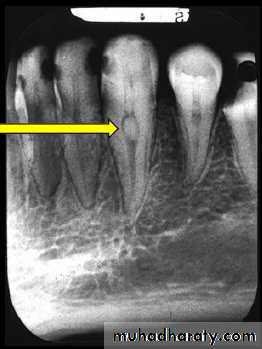

6) Internal root resorption Internal resorption is initiated within the pulp cavity and results in loss of substance from dentinal tissue.EtiologyExact etiology is unknown. Patient often presents with history of trauma, persistent chronic pulpitis, history of pulpotomy, crown preparation, force from orthodontic treatment, impacted teeth,…etc.

• Usually asymptomatic, recognized clinically through routine radiograph (especially in the root)• Pain occurs in cases of perforation of crown.

• “Pink Tooth” is the pathognomic feature of internal root resorption (especially in the crown).

• Radiographic changes:

– Radiolucent enlargement of pulp canal

– Original root canal outline distorted

– Bone changes are seen only when root perforation into periodontal ligament takes place.

• Pulp tests: Positive, though coronal portion of pulp is necrotic, apical pulp could be vital